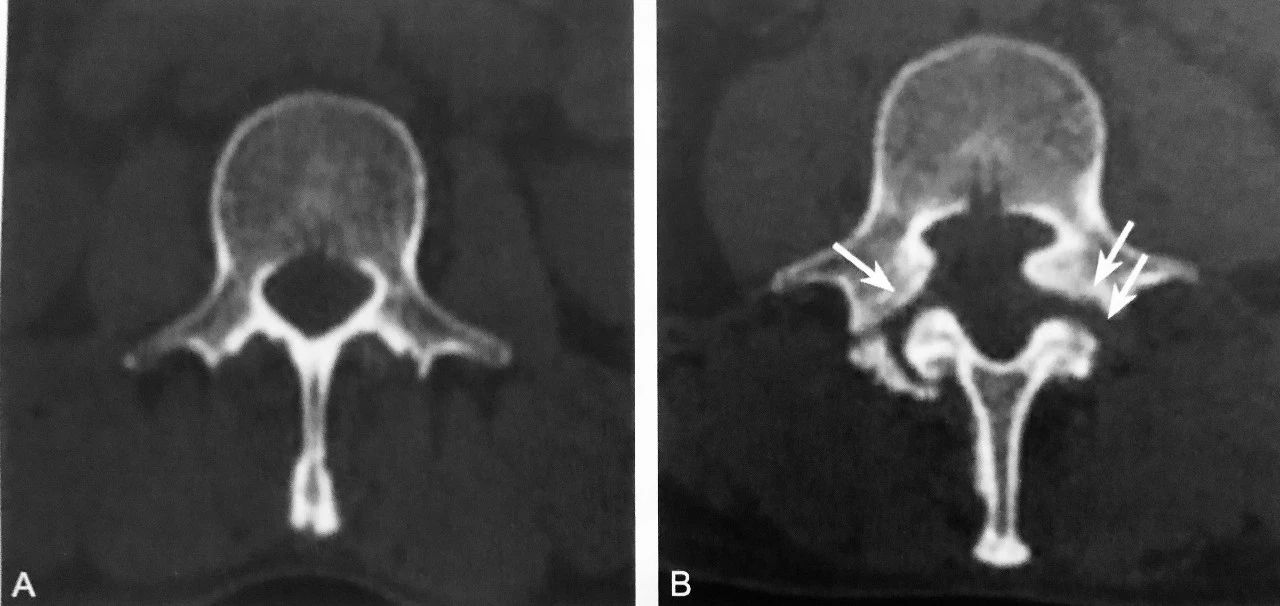

A.CT 横轴位图像,正常椎弓峡部层面骨性椎管呈完整环状结构,前部为椎体后缘,两侧为椎弓根序连于椎板,后部为棘突基底部围成;B.环裂征:双侧椎弓峡部崩裂(箭头),裂隙横跨峡部,断裂面形态不规则

判读要点:

1、椎弓峡部裂特征性直接征象;

2、在椎弓峡部平面 CT 横断位观察,以 RGCT 图像观察最佳;3、诊断时需除外脊椎裂、椎体畸形(蝴蝶椎)和手术椎板切除。